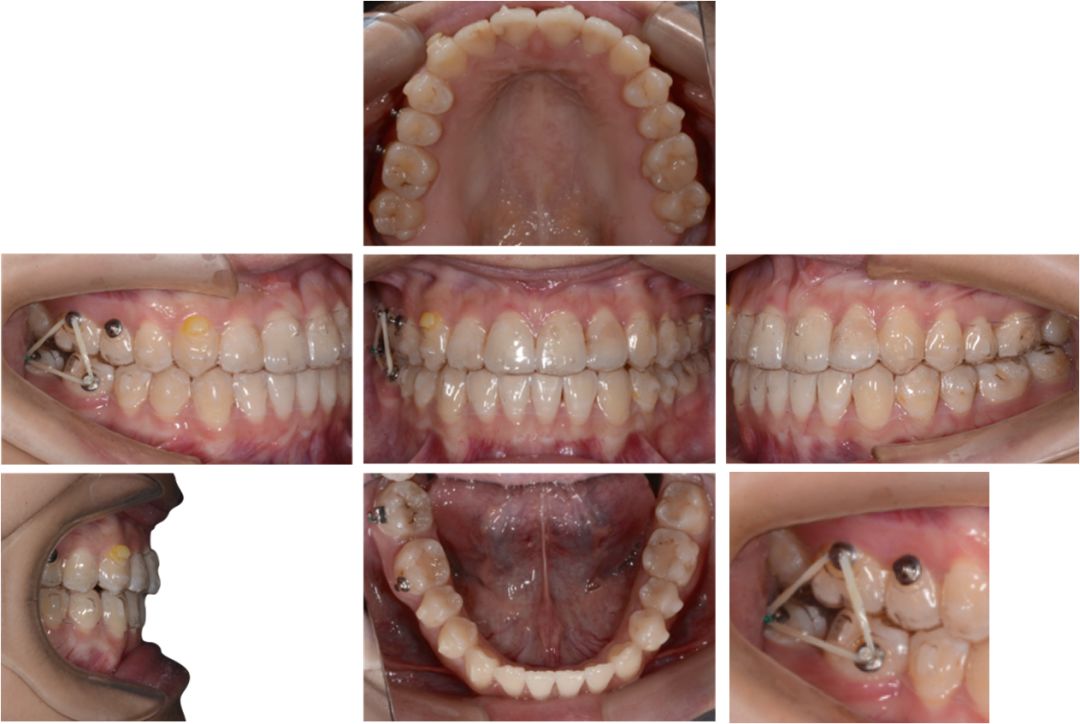

矫治中

第8副,矫治器与牙面贴合,矫治过程中配合III类牵引,有利于尖牙、磨牙关系的改善。

第20副,矫治器与牙面贴合,近中矩形附件使矫治器对47牙有较好的固位,47牙与45相对移动,磨牙尖牙关系改善。

第30副矫治器时,其余牙位矫治器还是比较贴合,但是47牙近中出现了低合与矫治器间隙变大,嘱患者使用咬胶,利用矫治器的力量竖直47牙。

第33副,由于47牙持续的前倾,我们进行了矫治设计的反馈,患者由于干扰的去除,咬合支点的前移,出现了颌位的后退。因为这个原因,实现了比矫治设计更好的尖牙磨牙关系。所以这次我们反馈时提交的是cr位的咬合记录。